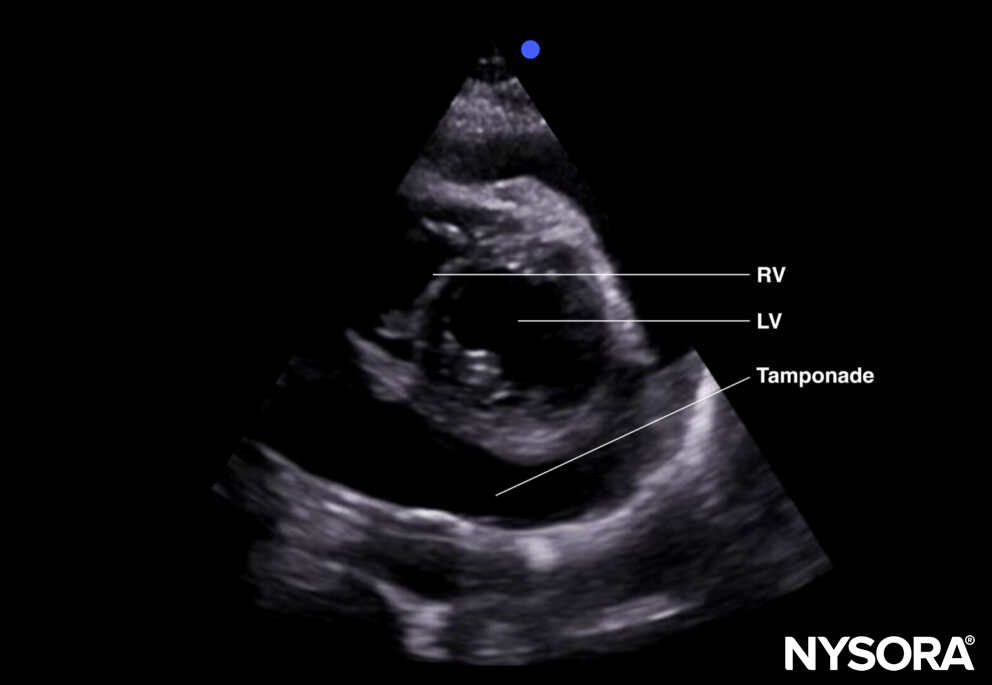

Tamponade (parasternal short-axis view).

Ultrasound features: Anechogenic layer between the heart and the pericardium:

- Size: Measure at end-diastole! (overestimation during systole)

- Small: < 1 cm

- Moderate: 1-2 cm

- Large: > 2 cm

- Dilated inferior vena cava without respiratory variation in case of tamponade: >2cm.

- Compression of the right atrium and right ventricle during diastole: more likely to result in tamponade.